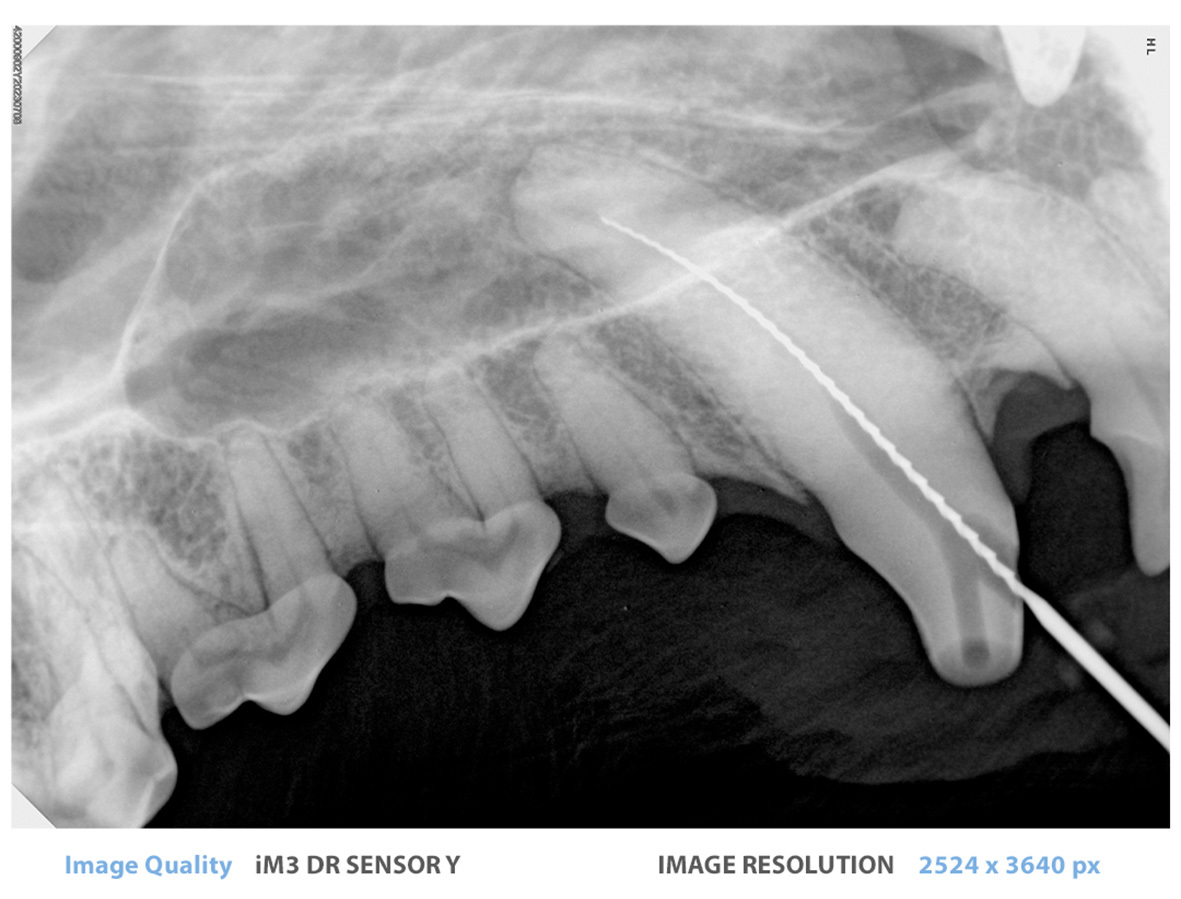

iM3 Sensor DR Y - Tamaño 4

El iM3 Sensor DR Y representa un avance significativo en tamaño para la odontología veterinaria en comparación con sus predecesores, ahora igualando las dimensiones de una placa CR tamaño 4 con 53.8 x 77.1 x 6.5 mm. Este aumento en el tamaño permite una área de imagen más amplia y completa, capturando estructuras dentales detalladas con mayor precisión.

Alta Resolución - ¡20 lp/mm! - Resolución Real

El iM3 DR Sensor Y utiliza un scintilador de Csl en lugar de los sensores basados en Gadox más comunes, lo que resulta en una resolución mucho mayor y menos ruido.

Con una impresionante resolución de 20 lp/mm (pares de líneas por milímetro), supera la resolución típica de 12 lp/mm que se encuentra en los sensores convencionales. Este nivel elevado de detalle y claridad en las imágenes capturadas permite evaluaciones más precisas y completas de la patología dental.

¡Amplio Rango Dinámico!

El iM3 DR Sensor Y cuenta con un WDR (o Rango Dinámico Amplio) incorporado. Cuanto mayor es el rango dinámico, mejor puede el sensor leer tanto en dosis altas como bajas de exposición a rayos X. Como resultado, el iM3 DR Sensor Y es muy tolerante y puede producir imágenes claras y nítidas en más condiciones que la competencia.

¡La Adición Perfecta!

Compatible con Vet-Exam Pro, el iM3 DR Sensor Y es una adición perfecta para los usuarios del iM3 CR 7 o CR 8, o del iM3 DR Sensor X (nuestro sensor DR tamaño 2).

Sin embargo, el iM3 DR Sensor Y se entrega con controladores TWAIN en lugar de su propia suite de software. Esta flexibilidad permite a los profesionales veterinarios utilizar su software de imagen preferido, brindándoles un mayor control y opciones de personalización para su flujo de trabajo de radiografía dental.

Al ser compatible con una amplia gama de programas que admiten TWAIN, el sensor DR asegura un proceso de integración suave y eficiente, eliminando la necesidad de instalaciones de software adicionales y simplificando la configuración general de la imagen. Los veterinarios pueden adoptar con confianza esta solución adaptable, mejorando sus capacidades diagnósticas mientras mantienen la conveniencia de su software de imagen dental seleccionado.